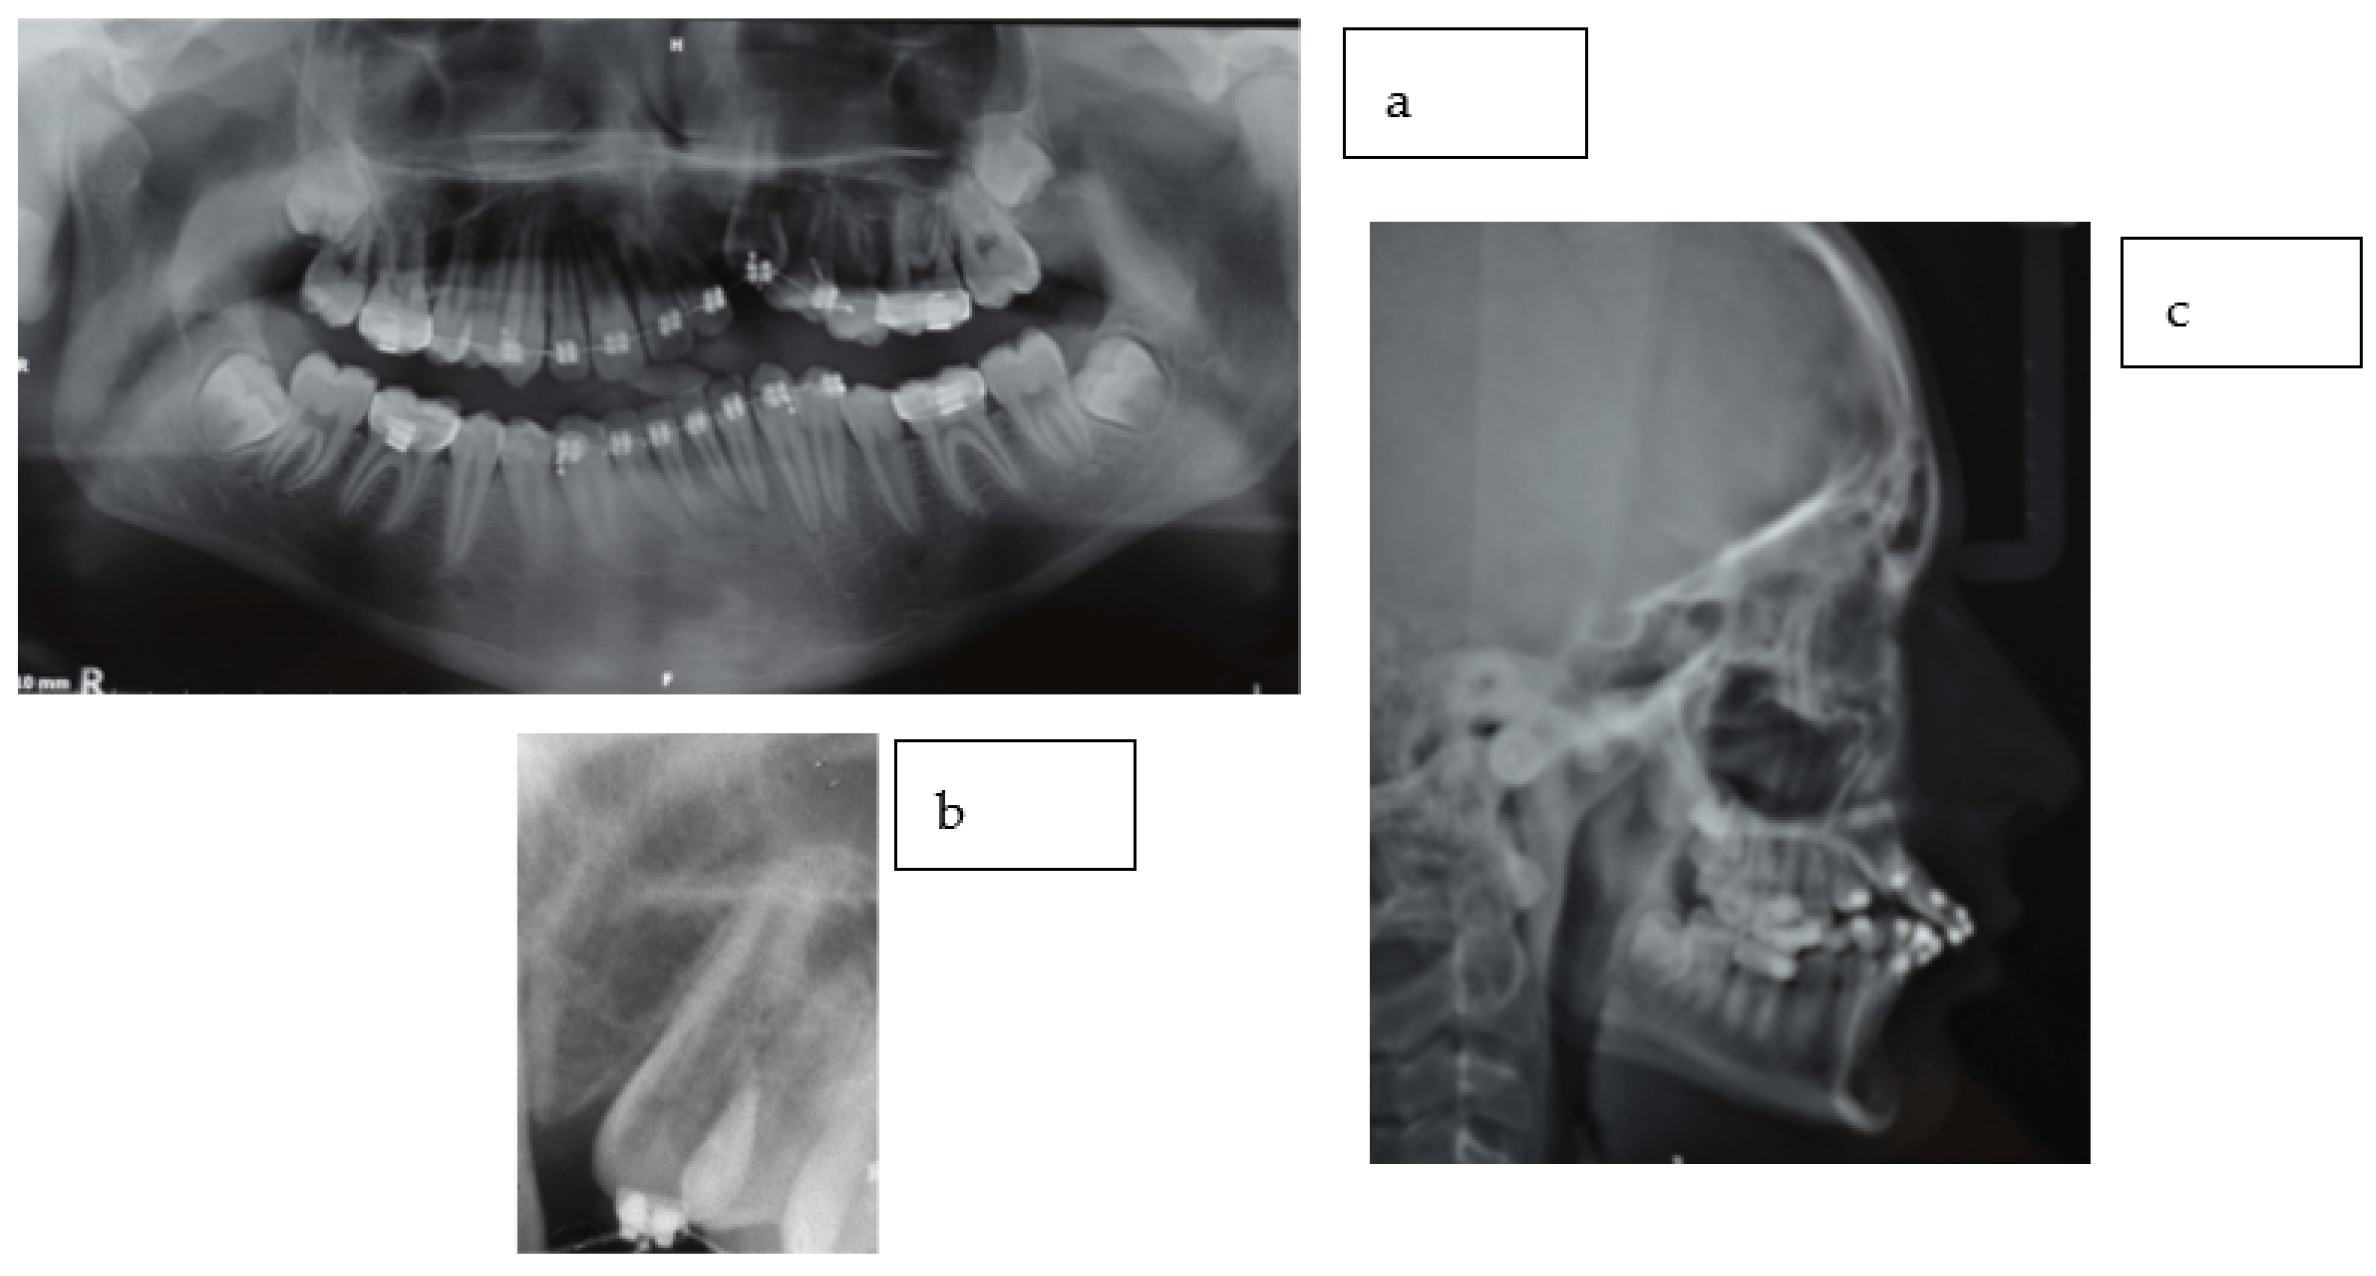

2.2. Radiographic Findings